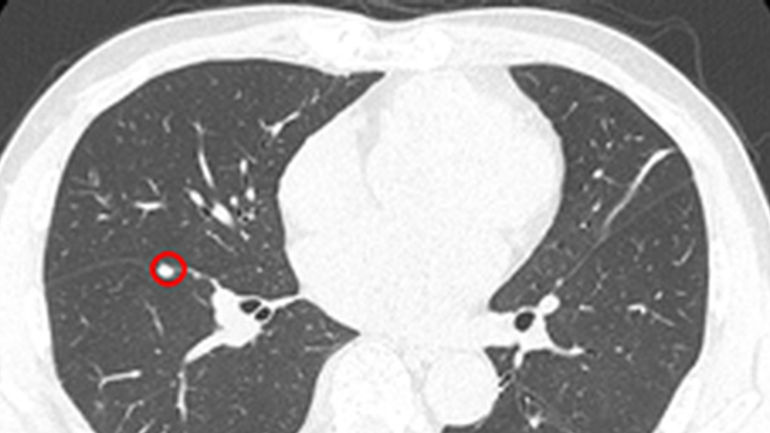

Đa ung thư nguyên phát là hiện tượng mà một người bệnh mắc nhiều hơn một loại ung thư với nguồn gốc mô bệnh học khác nhau, không phụ thuộc vào thời gian. Theo WHO, tỷ lệ mắc đa ung thư nguyên phát trên thế giới dao động từ 2,4% đến 17,2%.

Tiến bộ trong sàng lọc và chẩn đoán đã tăng khả năng phát hiện đa ung thư nguyên phát ở mọi giai đoạn. Có hai loại đa ung thư nguyên phát: đồng thời (synchronous) và liên tiếp (metachronous). Tiên lượng bệnh phụ thuộc vào vị trí khối u, giai đoạn bệnh, và thời gian chẩn đoán.

Khám phát hiện ung thư phổi và ung thư đường mật cùng lúc đặt ra thách thức lớn trong điều trị. Các yếu tố như vị trí khối u, giai đoạn bệnh, và thời gian chẩn đoán đều ảnh hưởng đến tiên lượng của bệnh nhân.